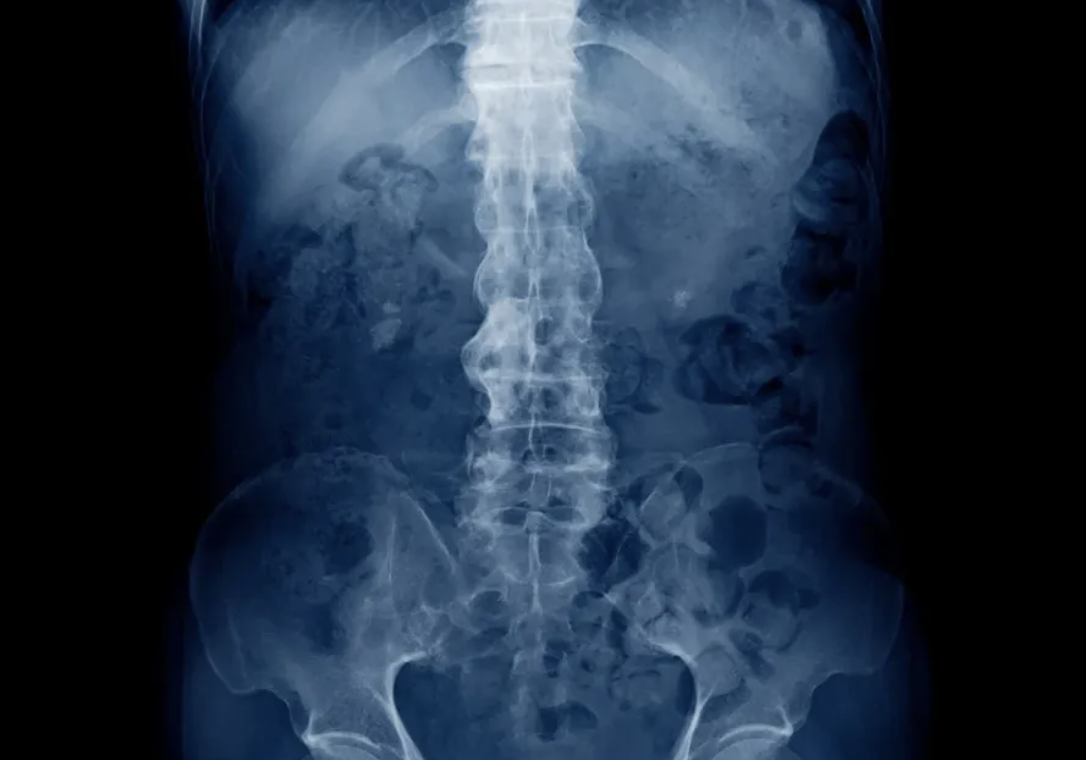

What are the hallmark radiographic findings in ankylosing spondylitis?

• X-ray findings: Bilateral sacroiliitis, sclerosis, erosions, ankylosis, and ‘bamboo spine.’

• MRI findings: Early inflammation, sacroiliac joint erosions, and sclerosis; performed if the X-ray is negative.

Ankylosing spondylitis is a clinical diagnosis based on symptoms of inflammatory back pain, loss of spinal mobility, and sacroiliitis. Confirmation is made using X-ray or MRI of the sacroiliac joints and spine to identify erosions, ankylosis, sclerosis, or bamboo spine.